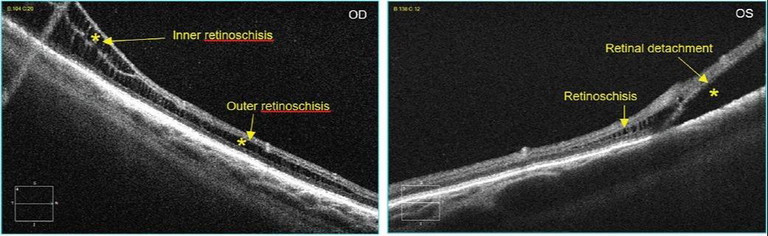

• Knowledge of the disease process and presentation will guide you in what to look for and capture (e.g., knowing the difference in presentation between retinoschisis and retinal detachment will enable you to identify an appropriate scan pattern, direction and location to collect information that best supports clinical diagnosis) (Figure 14, top right).

Figure 14. Scan location can assist with acquiring information needed to make a clinical diagnosis.